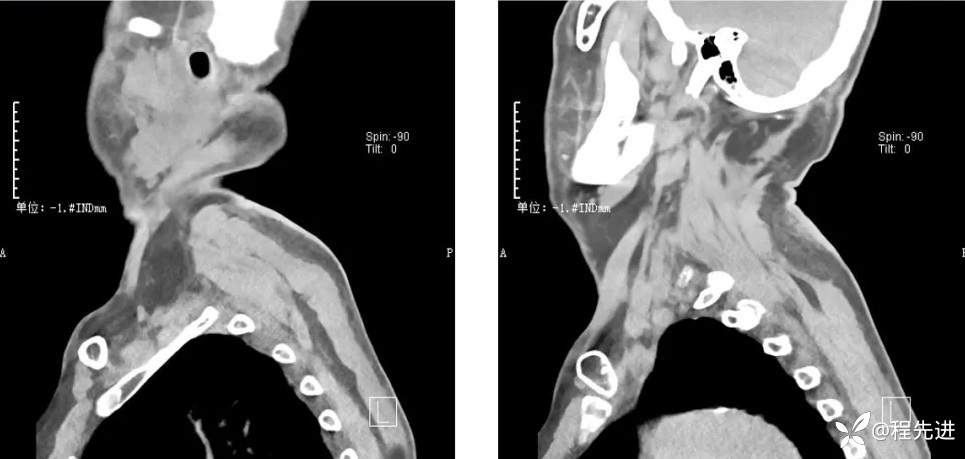

CT检查: